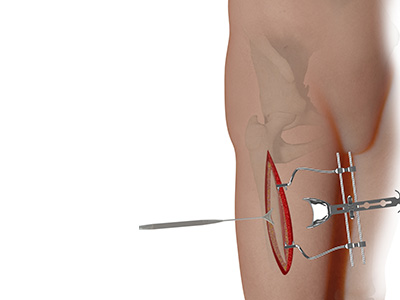

Direct Anterior Hip Replacement Direct Superior Hip Replacement

Direct Superior Hip Replacement Bikini Incision Hip Replacement

Bikini Incision Hip Replacement Hip Reconstruction

Muscle Sparing Anterior Hip Replacement Anterior Hip Replacement with Navigation

Rapid Recovery Hip Replacement Minimally Invasive Total Hip Replacement

Minimally Invasive Total Hip Replacement Complex Primary Hip Replacement